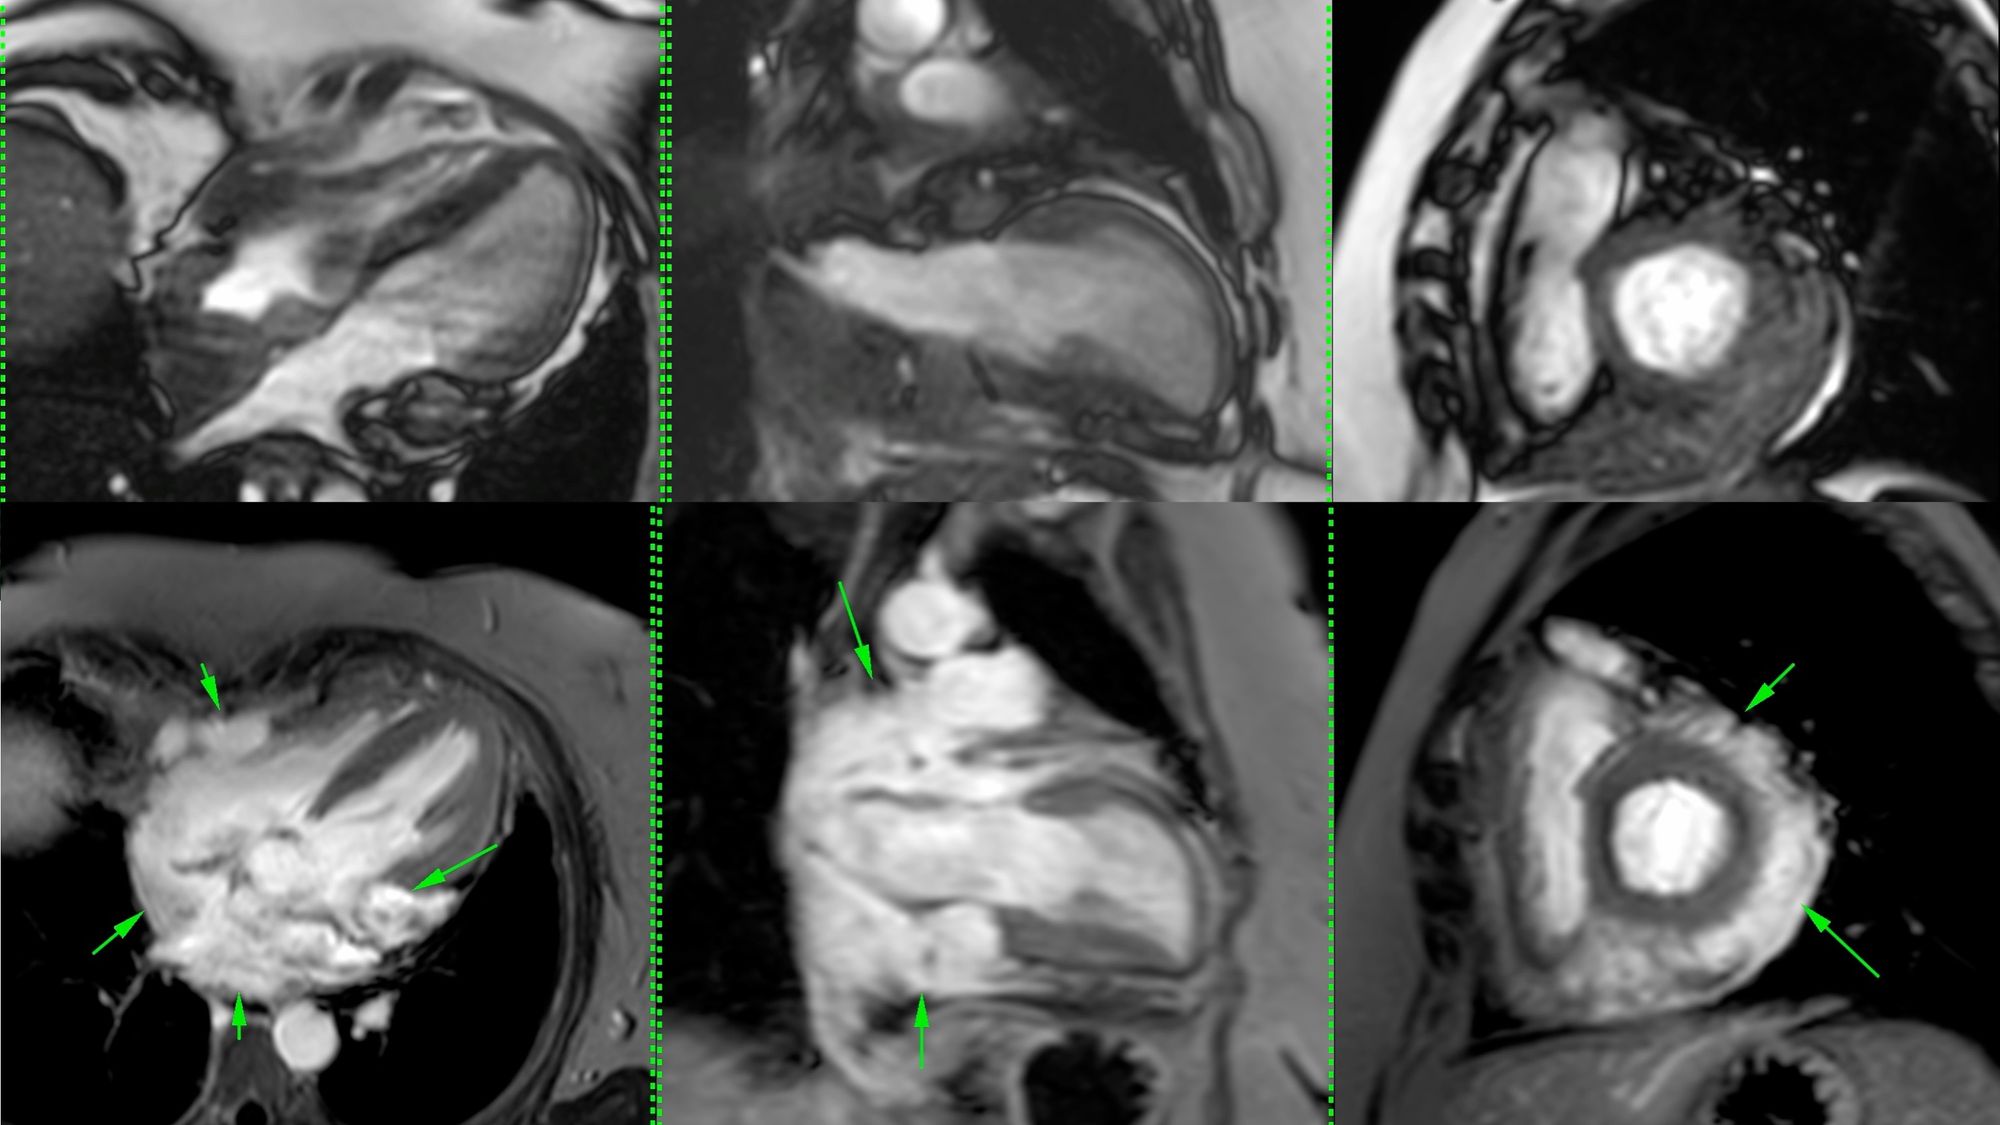

Today's case is about a 50-years old patient with pericardial effusion for 13 years, who came for a cardiac MRI, which showed a right atrial and interatrial septal mass with pericardial soft tissue and coronary artery encasement.

This led to a PET/CT and a biopsy and an unusual diagnosis.